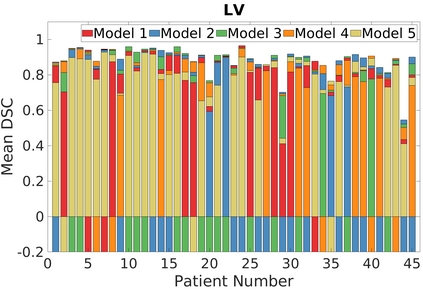

Deep Convolutional Neural Networks (DCNNs) are used extensively in biomedical image segmentation. However, current DCNNs usually use down sampling layers for increasing the receptive field and gaining abstract semantic information. These down sampling layers decrease the spatial dimension of feature maps, which can be detrimental to semantic image segmentation. Atrous convolution is an alternative for the down sampling layer. It increases the receptive field whilst maintains the spatial dimension of feature maps. In this paper, a method for effective atrous rate setting is proposed to achieve the largest and fully-covered receptive field with a minimum number of atrous convolutional layers. Furthermore, different atrous blocks, shortcut connections and normalization methods are explored to select the optimal network structure setting. These lead to a new and full-scale DCNN - Atrous Convolutional Neural Network (ACNN), which incorporates cascaded atrous II-blocks, residual learning and Fine Group Normalization (FGN). Application results of the proposed ACNN to Magnetic Resonance Imaging (MRI) and Computed Tomography (CT) image segmentation demonstrate that the proposed ACNN can achieve comparable segmentation Dice Similarity Coefficients (DSCs) to U-Net, optimized U-Net and hybrid network, but with significantly reduced trainable parameters due to the use of full-scale feature maps and therefore computationally is much more efficient for both the training and inference.